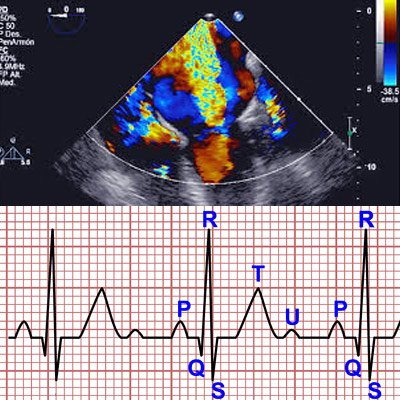

• ● Electrocardiograma

• ● Ecocardiograma Doppler